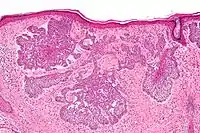

Nodular basal-cell carcinoma

Nodular basal-cell carcinoma (also known as "classic basal-cell carcinoma") accounts for between 50% and 80% of all BCC.[2] It most commonly occurs on the sun-exposed areas of the head and neck.[2] Histopathology shows aggregates of basaloid cells with well-defined borders, showing a peripheral palisading of cells and one or more typical clefts.[17] Such clefts are caused by shrinkage of mucin during tissue fixation and staining.[18] Central necrosis with eosinophilic, granular features may be also present, as well as mucin. The heavy aggregates of mucin determine a cystic structure. Calcification may be also present, especially in long-standing lesions.[17] Mitotic activity is usually not so evident, but a high mitotic rate may be present in more aggressive lesions.[17] Adenoidal BCC can be classified as a variant of NBCC, characterized by basaloid cells with a reticulated configuration extending into the dermis.[17]

Cleft.